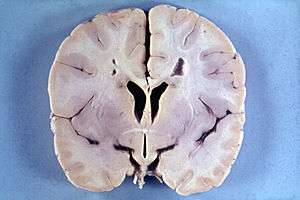

Brain of a 4-year-old boy with Alexander disease showing macroencephaly and periventricular leukomalacia (note brownish discoloration around the cerebral ventricles)